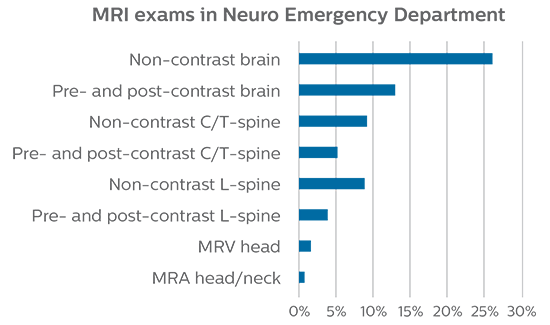

Growth of MRI in the Neuro Emergency Department

“Before, when patients received CT in the ED, it was quite common that they would need an MRI afterwards. However, in the four months that I have logged data for this study, I have not become aware of a single patient that underwent MRI in the ED and had to come back for repeat imaging, probably because the protocols are so robust. Patients with complicated cases requiring specialty acquisition types are the most common reason for recalls at our institution.”

“Our results show that a dedicated MRI in the ED can be effectively implemented; patient turnaround times with MRI were on par with CT. Interestingly, even though the MRI exam protocols were shortened, this robust yet rapid scanning still yielded good quality images, further improving our workflow and almost eliminating the need for repeat scans or follow-up scans. So, we’re heading towards first time right imaging,” says Dr. Karis.

At St. Joseph’s Hospital and Medical Center, the dedicated MRI system in the ED has been shown to efficiently provide high quality MR images that assist physicians in making informed decisions on patient diagnoses and take a more definitive decision on follow-up. The decision to have a dedicated ED MRI has resulted in rapid patient turnaround, efficient patient management, and substantial reductions in radiation dose.